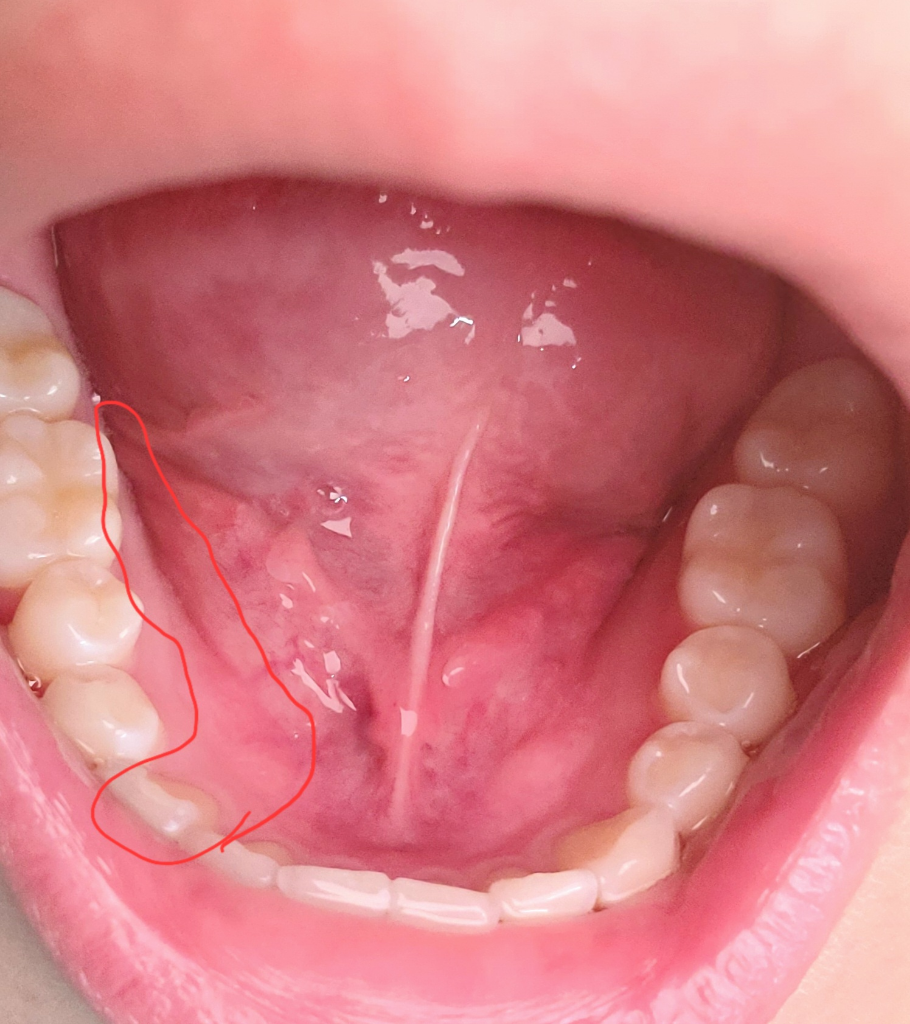

이빨 밑 잇몸 안쪽이랑 바깥쪽이 엄청 아파요

진짜 미친듯이 욱씬거리는데 충치도 없고 치석 때문인가 싶어서 4일 전에 스케일링도 받고 왔습니다 치위생사님이 피가 좀 났다고는 하셨는데 어디서 났는지는 모르겠어요 근데 스케일링 받고 4일이나 지났는데 더 아픕니다ㅠㅠ 치석 때문이 아니었나 아니면 스케일링 이후 치석이 많았으면 원래 좀 통증이 있나요? 근데 진짜 말도 안나올 정도로 아프기 시작해요 6시부터 ㅠㅠ 내일 치과 갈건데 진짜 너어어어어어무 아파요ㅠㅠ 왼쪽 턱까지 아프고 미치겠어요ㅠ 왼쪽 아프다가 오른쪽 아프고 왼쪽 아프다 오른쪽 아프고 또 이빨은 세트로 똑같은 곳만 아파요 아랫니 4개 중심으로 붙은 양쪽들이 왼쪽 아팠다가 오른쪽 아팠다가 환장하겠네요 근데 지금 왼쪽에 통증이 너무 심해서 올려봅니다ㅠㅠ

• 2번 째 사진

사진으로는 크게 문제가 없는 것으로 보입니다 통증이 해당 부위에 지속이 된다면 해당 부위로 너무 강한 음식을 드시지 않았는지 확인해 보시고 아무런 이상이 없음에도 불구하고 통증이 있다면 신경병증인 원인일 수도 있습니다 치과에서 구강내과에서 진료를 받아 보는 것을 권해 드립니다

스켈링을 하고 나서 불편감이 잇을수 있습니다. 스켈링을 하는건 초음파 진동이 전달되기떄문에 치석이 많거나 염증이 잇다면 치아가 몇일동안으불편하실수 있습니다.